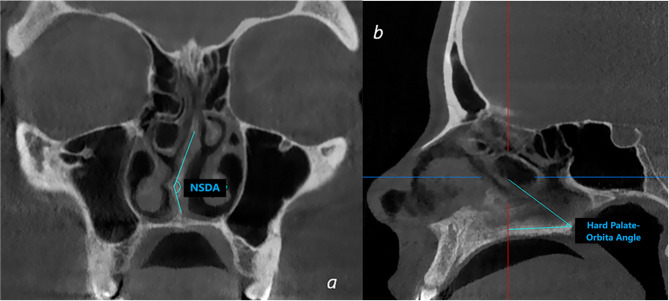

Parinaud管(PC)是位于上颌骨额突骨上的一种结构。在生长期间,鼻中隔的形状和鼻中隔偏曲(NSD)的存在可能影响面部形态学参数。本研究的目的是探讨PC的存在和NSD对面部形态学参数的影响。回顾性分析了200例患者的影像学资料。在CBCT图像上评估PC、NSD和腭眶角。显著性水平设为p = 0.05。在普通人群中PC的发生率较高,且在鼻偏斜角上差异无统计学意义(p < 0.05)。当左PC直径小于1 mm时,NSD角度有统计学意义上的增加(p

Parinaud's canal (PC) is a structure located on the processus frontalis ossis maxilla. During the growth period, the shape of the nasal septum and the presence of nasal septal deviation (NSD) may affect facial morphological parameters. The aim of this study is to investigate the presence of PC and the effect of the NSD on facial morphological parameters. Radiographic images of 200 patients were retrospectively reviewed. On the CBCT images PC, NSD and Palate-Orbita angle were evaluated. The significance level was set at p = 0.05. PC was found to be present at a high rate in the general population and its presence was not significantly different according to the angle of nasal deviation (p > 0.05). The angle of NSD was found to increase statistically when the left PC diameter was 1 mm or less (p < 0.05). The mean Hard Palate - Orbital Angle was 46.66 ± 8.43 degrees in individuals with the right PC while this angle was 36.50 ± 1.65 degrees in those without a canal. his study revealed that PC is common in the general population and has no significant relationship with NSD angle. While a decrease in the diameter of the left Parinaud's canal is observed as the NSD increases, the Hard Palate - Orbital Angle varies depending on the presence of the right PC. These findings indicate PC may play an important role in nasal and orbital anatomy.